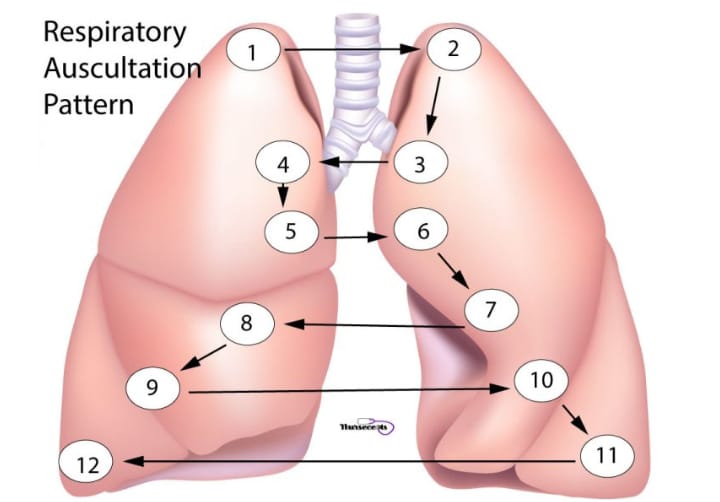

Auscultation (અસ્કલટેશન):

- અસ્કલટેશનમાં સ્ટેથોસ્કોપની મદદથી લંગ સાઉન્ડ સાંભળવામાં આવે છે.

- અસ્કલટેશનમાં ચેસ્ટની એન્ટેરિયર અને પોસ્ટેરીયર બાજુ ડાયાફ્રામની મદદથી લંગ સાઉન્ડ અસ્કલટેટ કરવામાં આવે છે. નીચે આપેલા પિક્ચરમાં દર્શાવ્યા મુજબ ચેસ્ટને અસ્કલટેટ કરવામાં આવે છે.